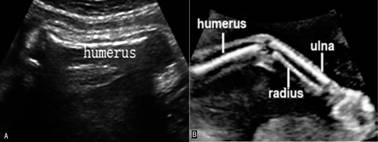

(一)上肢骨

显示胎儿颈部下方横切面、胸廓上部脊柱两侧前方各有一近似“S”形的强回声向外方展开,此为锁骨回声;在胸廓后方显示为三角形的强回声为肩胛骨(图2 SC);肩胛骨上方外侧在肩峰处与锁骨接近;以此为中心旋转探头即可显示出肱骨(humerus)回声(图3A);沿肱骨追踪扫查即能显示尺骨(ulna)和桡骨(radius)(图3B)。尺骨较长,上粗下细,与小指相连;而桡骨则相反,上细下粗,与大拇指相连。尺桡骨可显示出交叉现象。沿尺桡骨向下扫查,即可见胎儿手部,正常时胎手姿势自然呈握拳状,活动时,五指伸开时可显示手指数目及姿势。

图3 胎儿上肢骨声像图